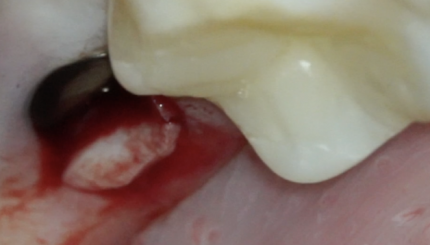

37 АДГЕЗИВНАЯ ФИКСАЦИЯ КЕРАМИЧЕСКОЙ НАКЛАДКИ